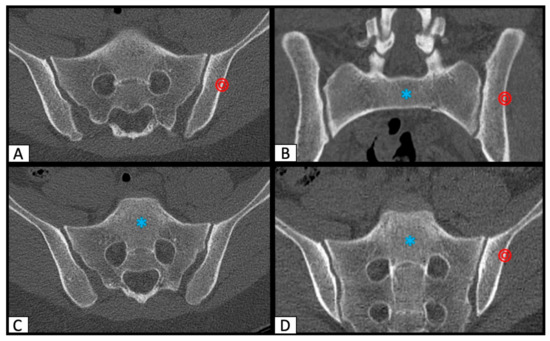

2.1. Determination of SI Screw Corridor

2.2. Image Processing with the Slice Fusion Method

3. Results